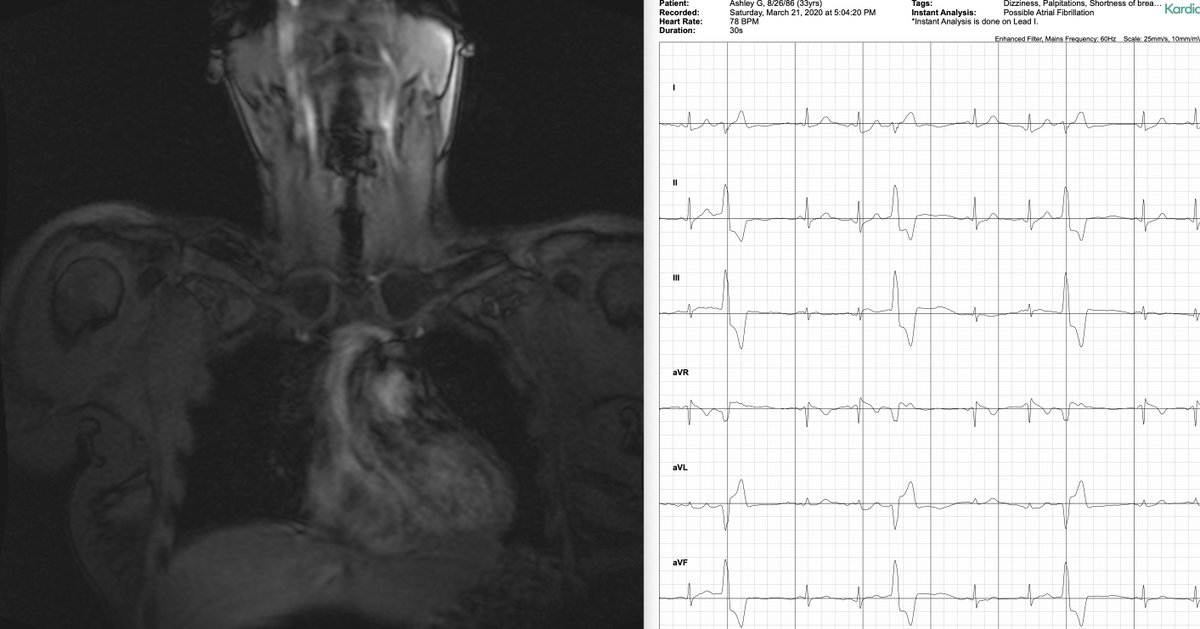

image of mri of chest and EKG results showing arrhythmia